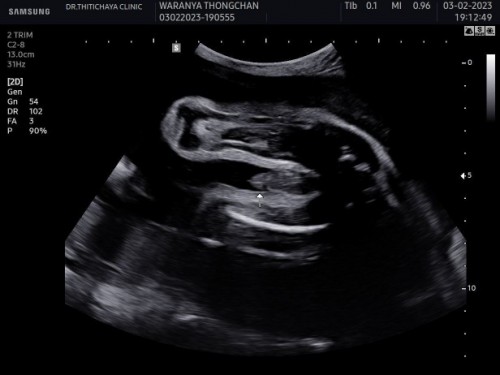

ซาวด์ตอน 28 สัปดาห์คะ

อยากให้แม่ๆช่วยดูหน่อยจ้ะ ว่าผู้หญิงหรือผู้ชาย#คุณแม่ๆช่วยแนะนำหน่อยค่ะ #ขอบคุณสำหรับคำตอบค่ะ

แบบนี้หญิง หรือชายค่ะ

ชายค่ะเเม่ ปลายเจี๋ยวเเหลม😂😂

ผู้ชายค่ะแม่ เหมือนลูกอัณฑะ เลยค่ะ

Baby boy ชัดเจนมากๆ ❤️❤️❤️❤️❤️❤️

ผู้ชายค่ะคุณแม่เป็นพวงเลย